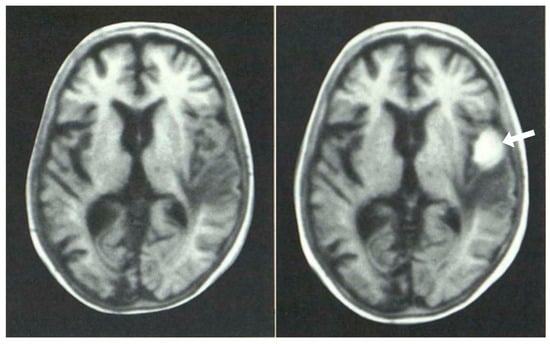

Figure 7.

Multiple sclerosis (MS): CT (left) and inversion recovery (IR) (right) (November 1981) [7]. Two larger lesions are seen on the CT image (left, arrows). These are also seen on the IR image (right, arrows). There are an additional six lesions seen in the periventricular white matter on the IR image (arrows). The additional lesions are seen in normal appearing white matter on the CT image.